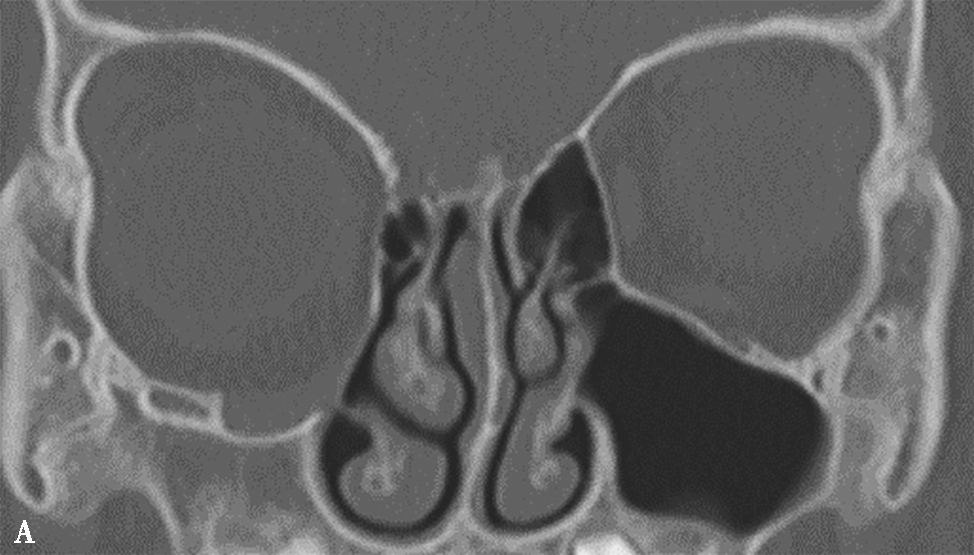

5.筛泡(bulla ethmoidalis)

即中组筛房,位于鼻丘后,由1~3个气房构成,内下壁与筛骨钩突间形成半月裂间隙。筛泡过度气化,可能造成筛漏斗及半月裂狭窄,影响引流;过度气化至眶下壁时,称为眶下气房,又称Haller气房,也可能影响上颌窦的引流(图1-3-6)。

图1-3-6 筛泡解剖变异

A.双侧Haller气房;B.左侧筛大泡